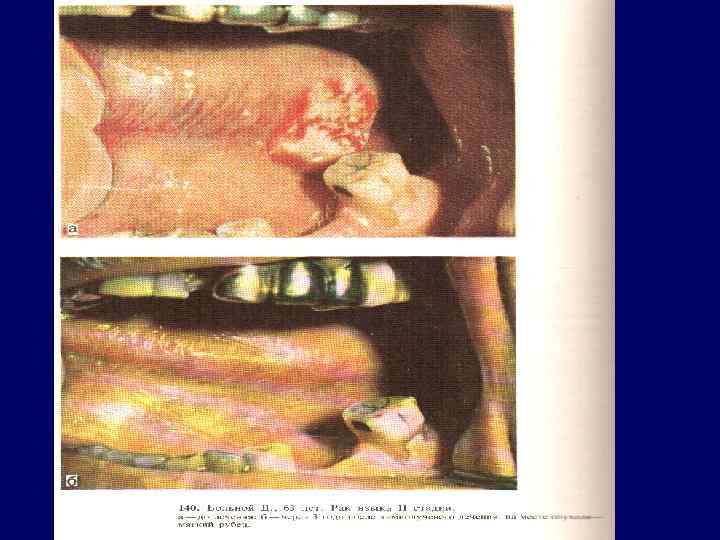

Рак языка 60 -70% - с/3 боковой поверхности и более 20% в корне языка; Плоскоклеточный рак, в корне лимфоэпителиома, аденокарцинома – 1, 5 -3% из малых слюнных желез в языке. Течение рака неблагоприятное, для прогноза имеет значение локализация опухоли. Рак корня языка (III злокачественности плоскоклеточный и лимфоэпителиома) обладает быстрым ростом, дает ранние и частые метастазы в регионарные глубокие шейные лимфоузлы. Рак в среднем и переднем отделах языка (I и II степень) метастазирует в подбородочные, нижнечелюстные и глубокие шейные лимфоузлы

Рак языка 60 -70% - с/3 боковой поверхности и более 20% в корне языка; Плоскоклеточный рак, в корне лимфоэпителиома, аденокарцинома – 1, 5 -3% из малых слюнных желез в языке. Течение рака неблагоприятное, для прогноза имеет значение локализация опухоли. Рак корня языка (III злокачественности плоскоклеточный и лимфоэпителиома) обладает быстрым ростом, дает ранние и частые метастазы в регионарные глубокие шейные лимфоузлы. Рак в среднем и переднем отделах языка (I и II степень) метастазирует в подбородочные, нижнечелюстные и глубокие шейные лимфоузлы

Рак языка (экзофитная форма)

Рак языка (экзофитная форма)

Рак боковой поверхности языка (язвенная форма)

Рак боковой поверхности языка (язвенная форма)